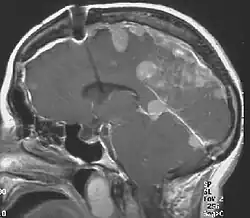

Die Neurofibromatose Typ II (NF II), auch als zentrale Neurofibromatose bezeichnet, ist eine erbliche Tumorerkrankung. Ihr Hauptmerkmal ist das Vorkommen von gutartigen Hirntumoren, die sich symmetrisch im Bereich beider Hör- und Gleichgewichtsnerven entwickeln. Die meisten Patienten mit dieser Erkrankung leiden auch an Veränderungen der Augen. Ursache der NF II sind Mutationen eines Gens, das vermutlich Einfluss nimmt auf Form und Wanderungsverhalten bestimmter Zelltypen. Da die NF II genetisch bedingt ist, ist eine Heilung nicht möglich. Die Behandlung besteht in der Entfernung von Tumoren im Bereich des Gehirns und Rückenmarkes sowie operativer Eingriffe im Bereich der Augen und der betroffenen Hirnnerven. Die NF II ist etwa zehnmal seltener als die häufigste Form der Neurofibromatose, die periphere Neurofibromatose Typ 1 (Morbus Recklinghausen).

Das Kern- oder Kardinalsymptom der Erkrankung sind die beidseitigen gutartigen Tumoren des Hörnervs (sog. bilaterale Akustikusneurinome). Durch dieses Symptom ist die Krankheit definiert.

- Der Nachweis von bilateralen Akustikusneurinomen mittels bildgebender Verfahren.